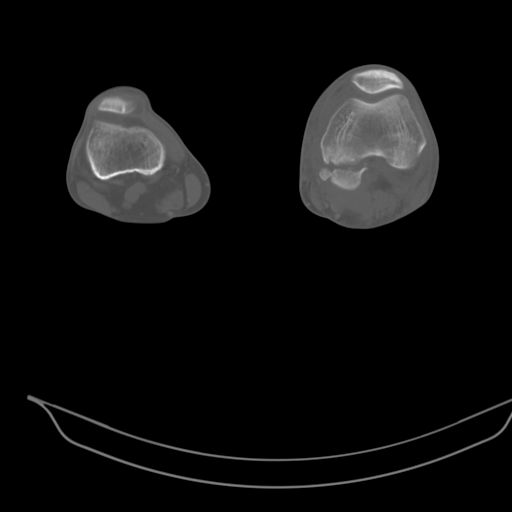

CT shows major bony fragments which are markedly rotated .With this amount of bony damage,you probably should attempt to get reasonably loooking knee with ORIF and thn if he needs a TKR due to pain a few years from now, then tleast you have something looking like a knee that you can replace rather than having to use revision knee for a primary TKR now. 4 weeks is not too long .what is the condition of soft tissues?

При внутрисуcтавных переломах трехмерные (3D) изображения, кроме красивого снимка, не дают полную информацию о состоянии отломков, самыми информативными являются корональные срезы на КТ и обычная длинная ренгенограмма конечности для сравнения оси конечности.

Фронтальные внутрисуставные переломы мыщельков бедра, так называемые Hoffa fracture, не частые, но встречающиеся переломы, в основном они связаны с травмой высокой энергией.